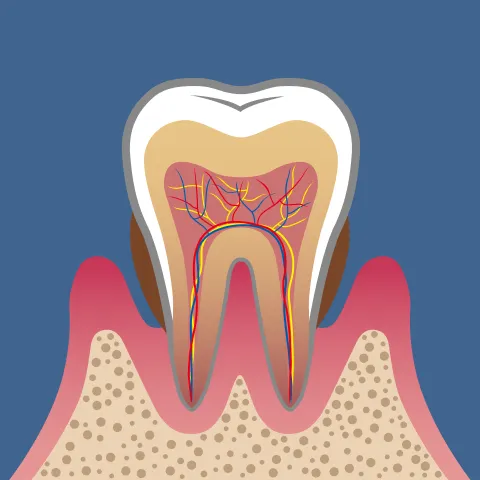

放置すると、炎症は歯ぐきの奥深くに広がり、「軽度歯周炎」へ進行します。

歯を支える骨(歯槽骨)が少しずつ溶け始め、歯と歯ぐきの間に「歯周ポケット」と呼ばれるすき間ができるのが特徴です。このポケット内は酸素が少なく、歯周病菌が繁殖しやすい環境のため、炎症がさらに進行していきます。

「中等度歯周炎」になると、歯槽骨の破壊が進行し、歯のぐらつきが現れ始めます。噛むと痛い、膿が出る、口臭が強くなる、歯ぐきが下がって歯が長く見える――といった症状が増えていきます。この段階では通常のクリーニングでは改善が難しく、「歯周外科治療」などの外科的なアプローチが必要になるケースもあります。